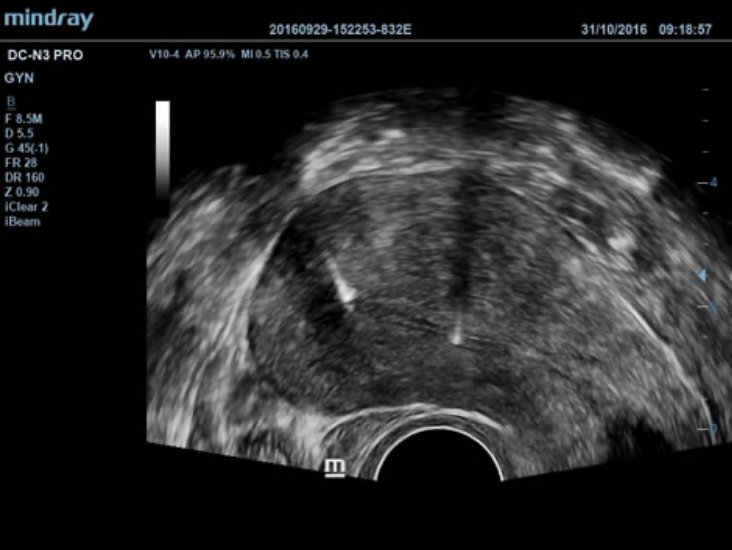

iClear?

Mejor calidad de imagen basada en la detecciĂłn automĂĄtica de estructuras.

- Bordes mĂĄs nĂtidos y continuos.

- Tejidos uniformes lisos.

- â?reas sin ecoâ mĂĄs limpias.